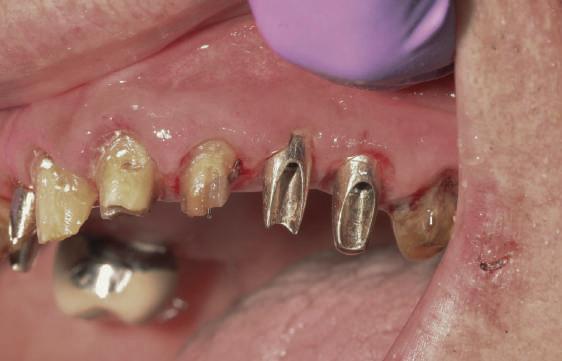

Cazul (3)

Refrezarea bonturilor individualizate

Pacientul prezenta dentiţie maxilară şi mandibulară eşuată datorită cariei secundare provocată de xerostomia post-iradiere. Pacientul suferise o disecţie cervicală radicală pentru înlăturarea carcinomului cu celule scuamoase la nivelul gâtului cu 9 ani înainte, urmată de radioterapie dar fără limită de ecranare. S-a utilizat o abordare stadializată pentru a evita protezele mobilizabile pe ţesuturile moi, extrem de uscate. Pacientul a optat pentru tratarea prioritară la nivel mandibular.

Fig. 9 prezintă bonturile de vindecare adiacente dinţilor naturali menţinuţi temporar, iar fig. 10 bonturile individualizate din prima etapă, inserate cu un contur gingival relativ bun şi fără recesie. Recesia era clar vizibilă în jurul tuturor bonturilor din prima etapă, după extracţiile adiacente şi plasarea implanturilor din a doua etapă (fig. 11). Atitudine: S-a decis îndepărtarea acestor bonturi şi amprenta corpului implantar al tuturor implanturilor astfel încât bonturile noi şi cele din prima etapă să fie frezate împreună pentru paralelism şi poziţionarea adecvată a marginii gingivale. Întrucât aceasta necesita îndepărtarea bonturilor din prima etapă care menţineau proteza provizorie, înainte de îndepărtarea tuturor bonturilor individualizate s-au plasat bonturi provizorii, cu scopul de a asigura poziţionarea adecvată şi dimensiunea verticală a restaurării provizorii. Aceste bonturi provizorii au menţinut apoi restaurarea temporară,

Cazul (3): Refrezarea bonturilor individualizate

Figurile

9. Bonturile de vindecare.

10. Bonturile individualizate în prima etapă.

11. Recesia evidentă în jurul bonturilor din prima etapă, după extracţiile adiacente şi inserarea implanturilor din faza a doua.

12. Bonturile refrezate şi noile bonturi individualizate.

în timp ce toate bonturile individualizate au fost fabricate şi/sau frezate în laborator. Fig. 12 prezintă plasarea bonturilor refrezate (la implanturile din prima etapă) şi bonturile individualizate noi (la cele din a doua etapă).